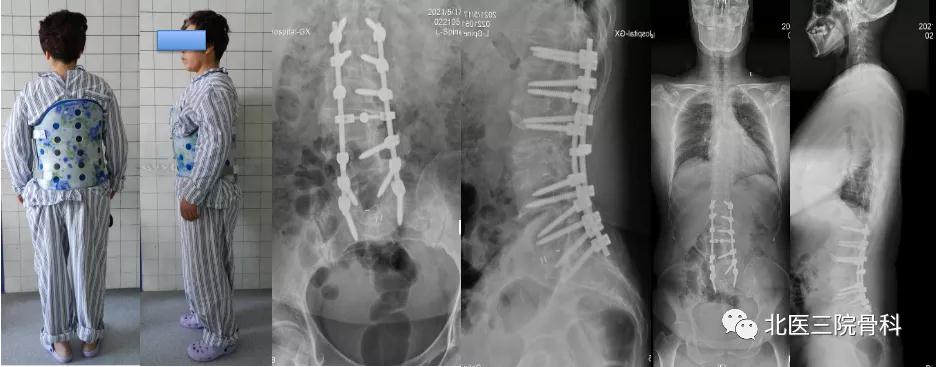

病例六

腰椎退变性侧弯大体照及影像学

(术前)

(术后)